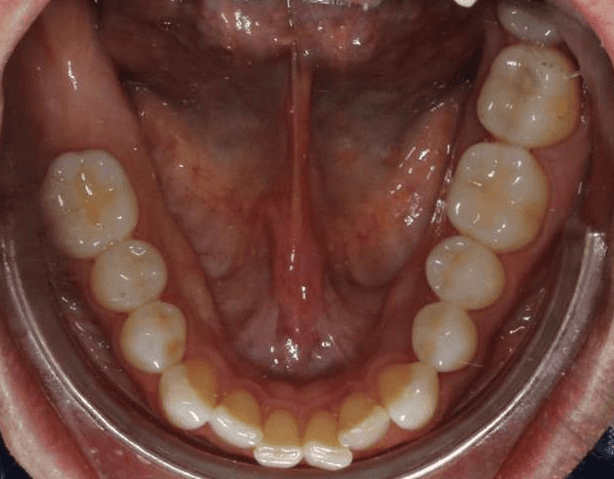

Initial treatment

INTRAORAL